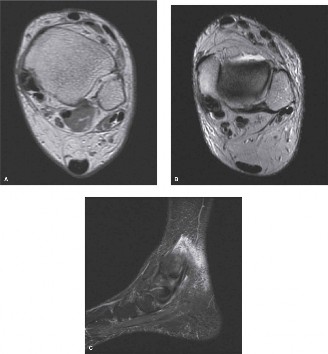

The patient was previously seen by another physician who ordered an MRI of the ankle (Fig. 5–29A–C).

Figure 5–29 A–C: MRI images of the ankle.

The correct answer is (E). The patient has stage 2 posterior tibial tendon deficiency (PTTD). Stage 1 PTTD includes tenosynovitis of the PTT without degeneration or deformity. Stage 2 PTTD is a flexible planovalgus deformity, which is passively correctable. MRI images show longitudinal split tearing and tendinopathy of the PTT, consistent with this finding. Stage 3 PTTD is a rigid flatfoot deformity, while stage 4 includes involvement of the tibiotalar joint as well as the foot. Initial conservative treatment for stage 2 PTTD can be with the use of an Arizona brace. A night splint would be more appropriate for the treatment of plantar fasciitis, and an ankle compression sleeve might be for lower extremity edema.